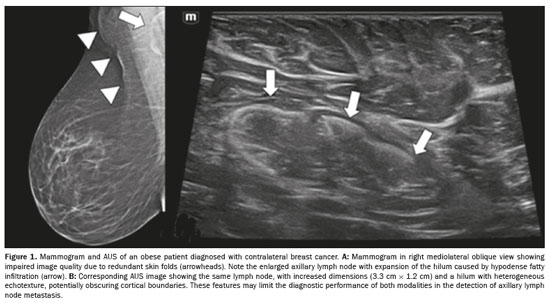

A high body mass index (BMI) may complicate axillary assessment by increasing lymph node dimensions due to fatty infiltration of the hilum (Figure 1), which may obscure subtle abnormalities and alter established morphological criteria for malignancy(16,17). Obesity may also hinder proper patient positioning during mammography (Figure 1A) and MRI(15–18), as well as compromising the clinical examination and ultrasound transmission due to thick subcutaneous fat in the axilla(16,19), as illustrated in Figure 1B. It is noteworthy that fat infiltration in contralateral axillary lymph nodes on MRI has been associated with a higher likelihood of metastases in obese women, independent of tumor characteristics, whereas BMI itself has not been shown to be a determining factor(20). Among obese patients, sentinel node detection rates tend to be lower and mapping failure rates tend to be higher(21–23).